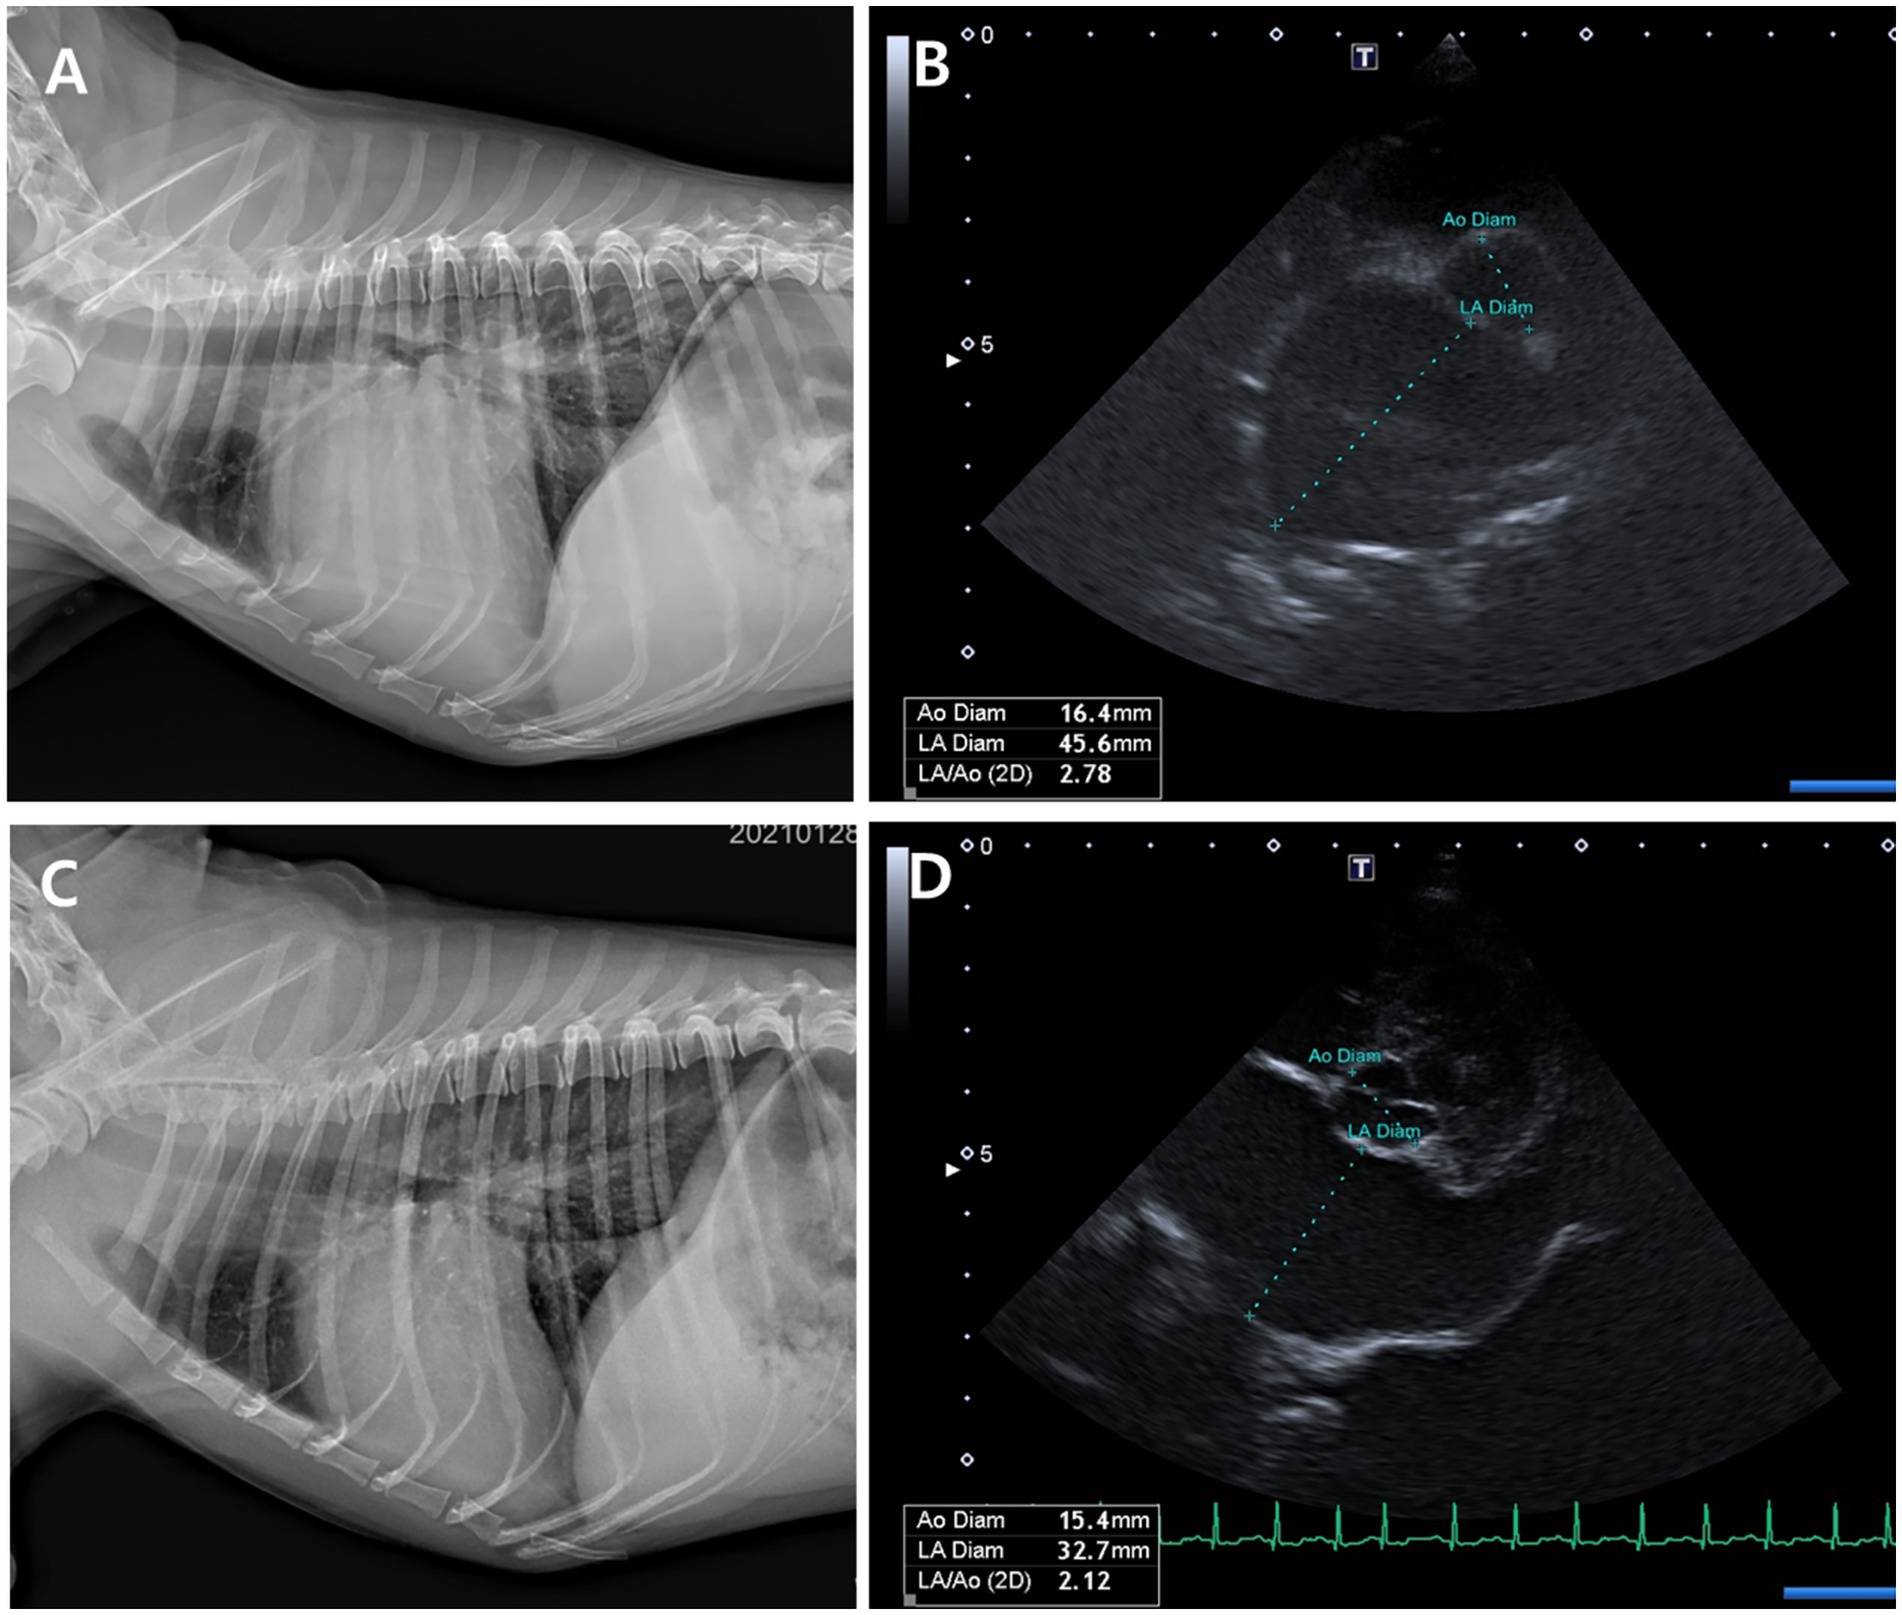

Figure 6. Thoracic radiographs (A, C) and echocardiographic images (B, D) from a Group 1 (test group) dog, taken before and 56 days after treatment with the combination tablet (ForteGold). Following treatment, the vertebral heart scale (VHS) and vertebral left atrial size (VLAS) on thoracic radiography decreased from 12.0 and 2.8 to 10.5 and 2.2, respectively (A, C). Similarly, the left atrial-to-aortic root diameter ratio (LA/Ao) on echocardiography was reduced from 2.78 to 2.1 (B, D).

Both groups demonstrated reductions in LA/Ao, LVIDd/Ao, and MVE values over time (Tables 3, 4; Figures 5, 6). The magnitude of improvement was greater and occurred earlier in the Group 1 (test group). Significant reductions in LA/Ao ratio were observed as early as Day 14 in Group 1 (p < 0.05), compared to Day 28 in Group 2 (control; Figures 5, 6).